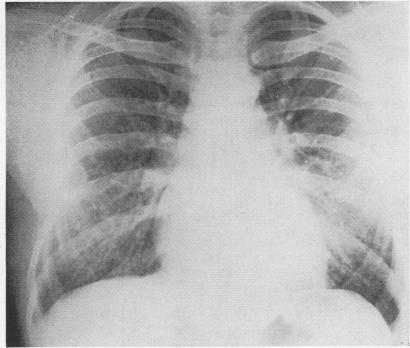

An epidemiological and environmental survey of 170 bagasse workers employed by a raw sugar producing company in Trinidad was carried out in order to assess the prevalence of respiratory symptoms and to determine if exposure to bagasse was associated with alterations in ventilatory capacity. The epidemiological survey failed to reveal a significantly increased prevalence of respiratory symptoms in the more exposed group but showed that the group of Indian workers who were regularly and continuously exposed to bagasse had a significantly lower ventilatory capacity than the control group. This diminished ventilatory capacity was demonstrated despite negligible dust concentrations in the plant. However, the possibility that persistent exposure to low concentrations of bagasse may be the cause must be considered. During a five-year period, 17 patients with bagassosis were seen, the clinical picture being similar to that described in extrinsic allergic alveolitis from other causes. The systematic variations demonstrated in some indices of ventilatory function in different racial groups are discussed.

为评估呼吸道症状的患病率,并确定接触甘蔗渣是否与通气能力改变有关,对特立尼达一家原糖生产公司雇佣的170名甘蔗渣工人进行了一项流行病学和环境调查。流行病学调查未能发现暴露程度较高组的呼吸道症状患病率显著增加,但显示经常持续接触甘蔗渣的印度工人组的通气能力明显低于对照组。尽管工厂内粉尘浓度可忽略不计,但仍显示出通气能力下降。然而,必须考虑长期接触低浓度甘蔗渣可能是原因这一可能性。在五年期间,共诊治了17例甘蔗渣肺患者,其临床表现与其他原因引起的外源性过敏性肺泡炎相似。文中讨论了不同种族群体通气功能某些指标中表现出的系统性差异。